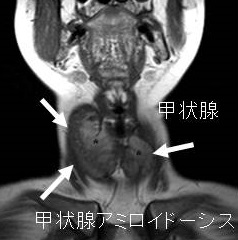

アミロイドーシスとは、通常なら可溶性の蛋白質が、様々な原因(加齢・遺伝・腫瘍・炎症など)によって、アミロイドと呼ばれる線維状の重合体をもつ不溶性蛋白を形成し、細胞外に沈着すると共に臓器障害を生じる疾患群です。甲状腺に沈着し甲状腺機能低下症(甲状腺アミロイドーシス)を来します。

- 老人性トランスサイレチンアミロイドーシス(老人性全身性アミロイドーシス、senile systemic amyloidosis;SSA);野生型トランスサイレチンを前駆蛋白としたアミロイドが主に心臓、肺、もちろん腎臓,副腎,甲状腺などに沈着[Lab Invest. 1983 Feb;48(2):231-40.]

- びまん性甲状腺腫大(amyloid goiter、アミロイド ゴイター):アミロイドが甲状腺に沈着し、甲状腺は腫大します。多発性骨髄腫が原因のALアミロイドーシスでは化学療法により甲状腺腫が縮小します